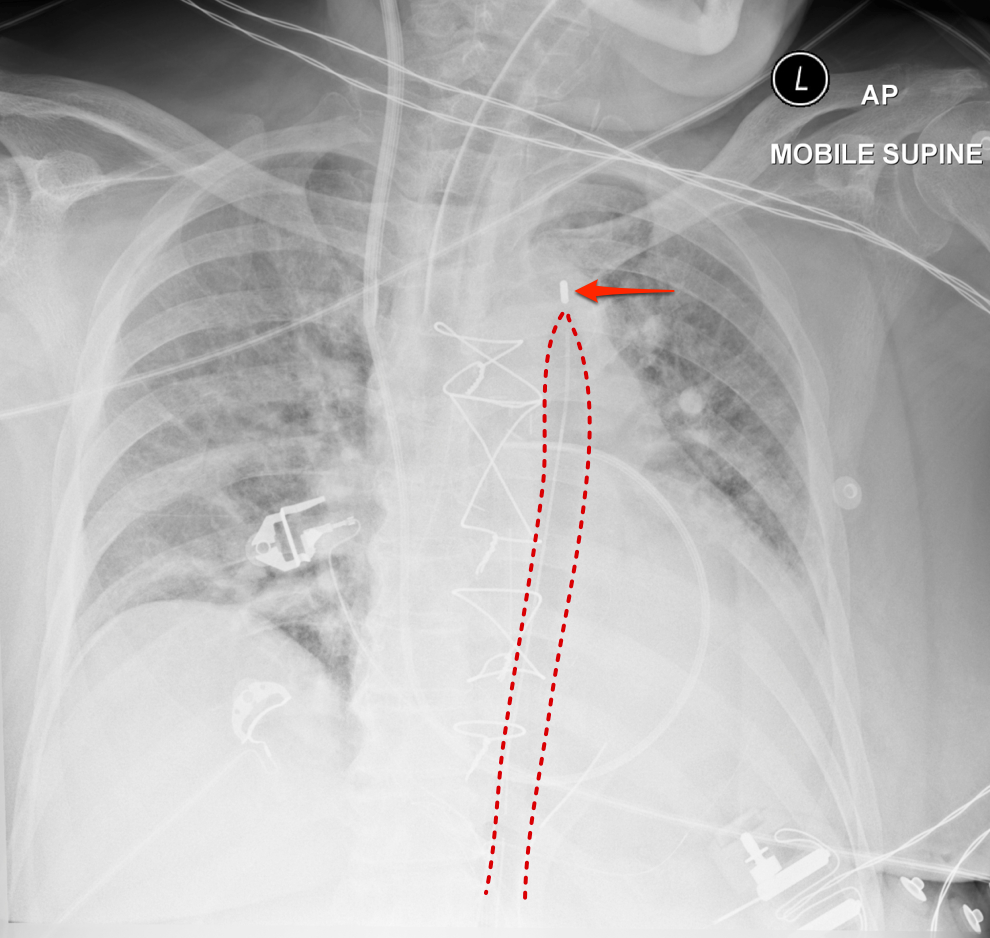

Where should the tip of an Intraaortic Balloon Pump (IABP) be?

Intraaortic Balloon Pump (IABP)

Tip should be located just distal to the takeoff of the left subclavian artery (LSA) and be 2–4 cm below aortic knob. Inflation may be seen during diastole.

The balloon should be located in the proximal descending aorta, just below the origin of the left subclavian artery. On a chest radiograph, it should be at the level of the AP window. This ideally results in the balloon terminating just above the splanchnic vessels 3.

Case courtesy of Assoc Prof Frank Gaillard, Radiopaedia.org, rID: 19299